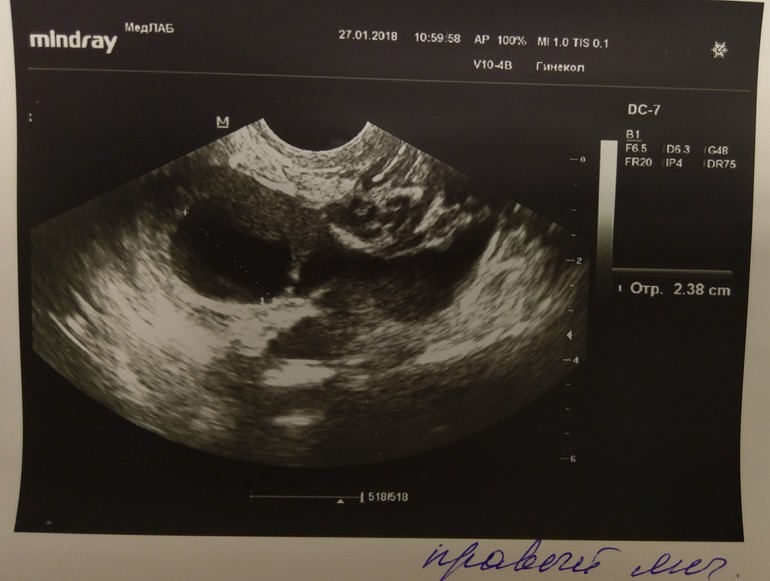

УЗИ на 12дц , ДФ 24мм

В ПЯ нашла ДФ на секундочку 24мм!!!!!! Эндик 10мм. Гиня сказала все отлично, и стараться сегодня.

Я правда не понимаю как так. Всплеск ЛГ был на 10дц, сегодня 12дц. БТ уже вверх полезла, сегодня 36.7 . Типа О должна сегодня быть по всем параметрам. Хз короче. То есть может и не лопнет мой мега большой фолликул .